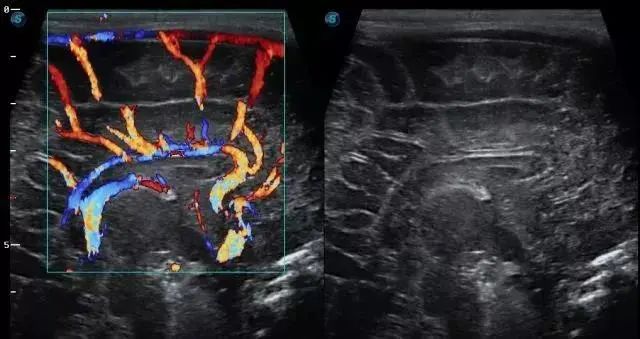

➤ D型:又称为多普勒超声诊断法。彩色多普勒可以在B超上叠加彩色的实时血流显像。以不同颜色显示血流的方向,色泽的深浅代表血流的流速。

彩超不是彩电,没有赤橙黄绿青蓝紫那么丰富的色彩。彩超是融合了彩色多普勒血流显像和黑白二维灰阶图像的超声诊断仪,只有在照血管的时候,才会有彩色。而且就只有红色和蓝色,没有其他。

如图,左边就是彩超图,右边就是B超图

彩超部分红蓝就是血流部分